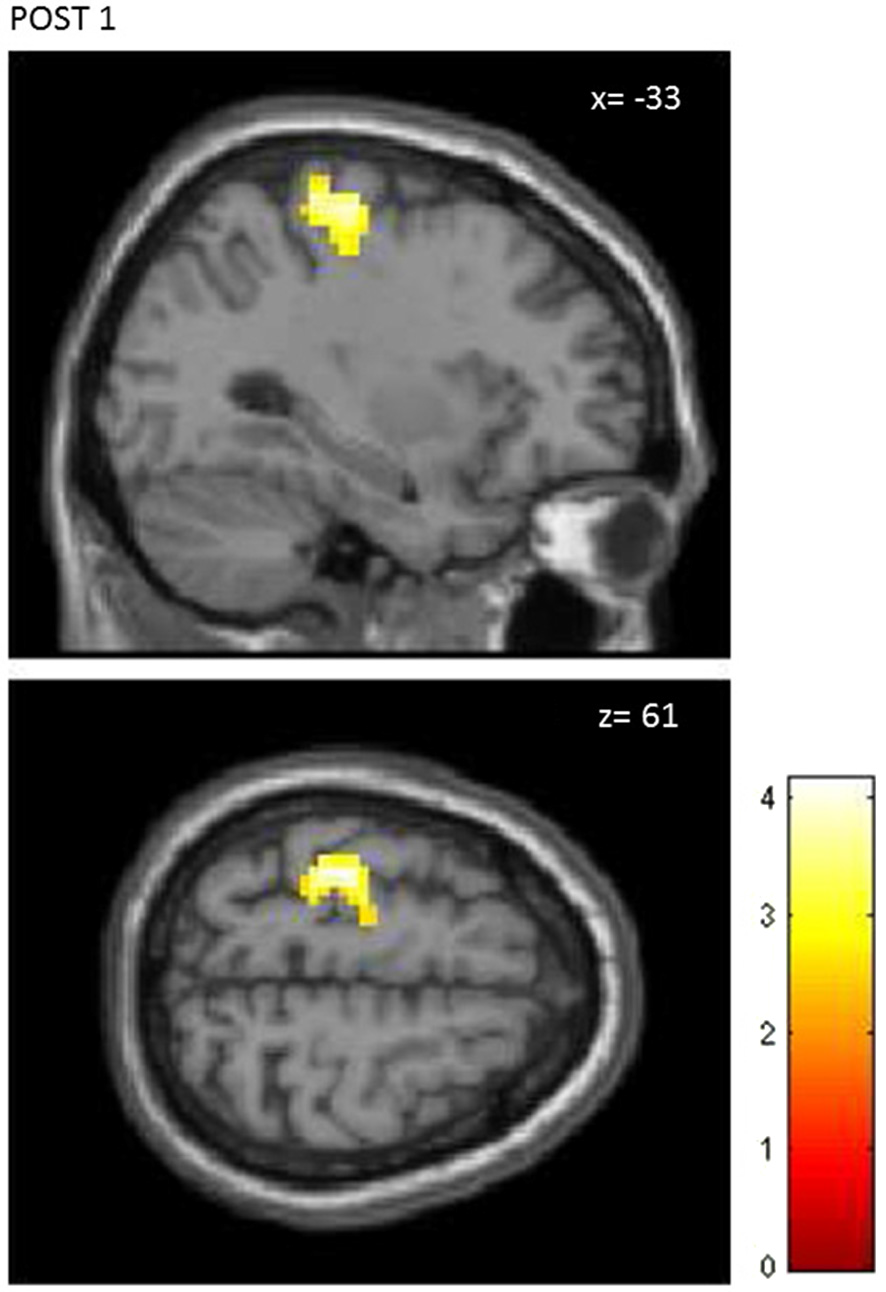

The first level analysis showed significant activation-related BOLD response induced by finger tapping for all participants (Ts peak > 12.81), therefore data from all 30 subjects (15 STIM, 15 NOSTIM) were taken for the second level statistical analysis. For both groups across all fMRI assessments, finger tapping activated the left precentral area (M1), left and right postcentral areas (S1), left supplementory motor area (SMA) and left and right cerebellum. The most remarkable differences in the maximum brain activation areas between the stimulated and the sham group after rPMS occurred within the contralateral M1 and S1. At baseline condition (PRE) the activation within these areas was comparable for both groups and in the ROI analysis between-groups differences were not found for M1 (p = 0.27) and for S1 (p = 0.53). Further random effects analysis showed significant difference in brain activation between the STIM and the NOSTIM group after rPMS (POST1), see Figure 4. Compared to the NOSTIM group an augmented BOLD response within the left sensorimotor cortex (precentral, postcentral) was revealed (T = 2.47), cluster peak (MNI, x = −33 mm y = −25 mm z = 61 mm). At the second post stimulation assessment (POST2) this effect was not present any more.

Figure 4

Random effects between-groups analysis. STIM vs. NOSTIM group after 25 Hz rPMS at lime level POST1. Significant changes in activation pattern within the left precentral/postcentral gyrus (p = 0.01, uncorrected, p < 0.05, corrected on cluster level).

Further, ROI analysis was carried out separately for M1 and S1. Post-stimulation effects were revealed only for M1. ANOVA showed significant interaction effect of Time × Group (F(2,56) = 3.45; p = 0.04). Main effect of Time only was found for the STIM group. Significant change in the contrast response between PRE and POST1 (p < 0.001) was shown in the post hoc analysis. Again at POST2 this effect was not present anymore.